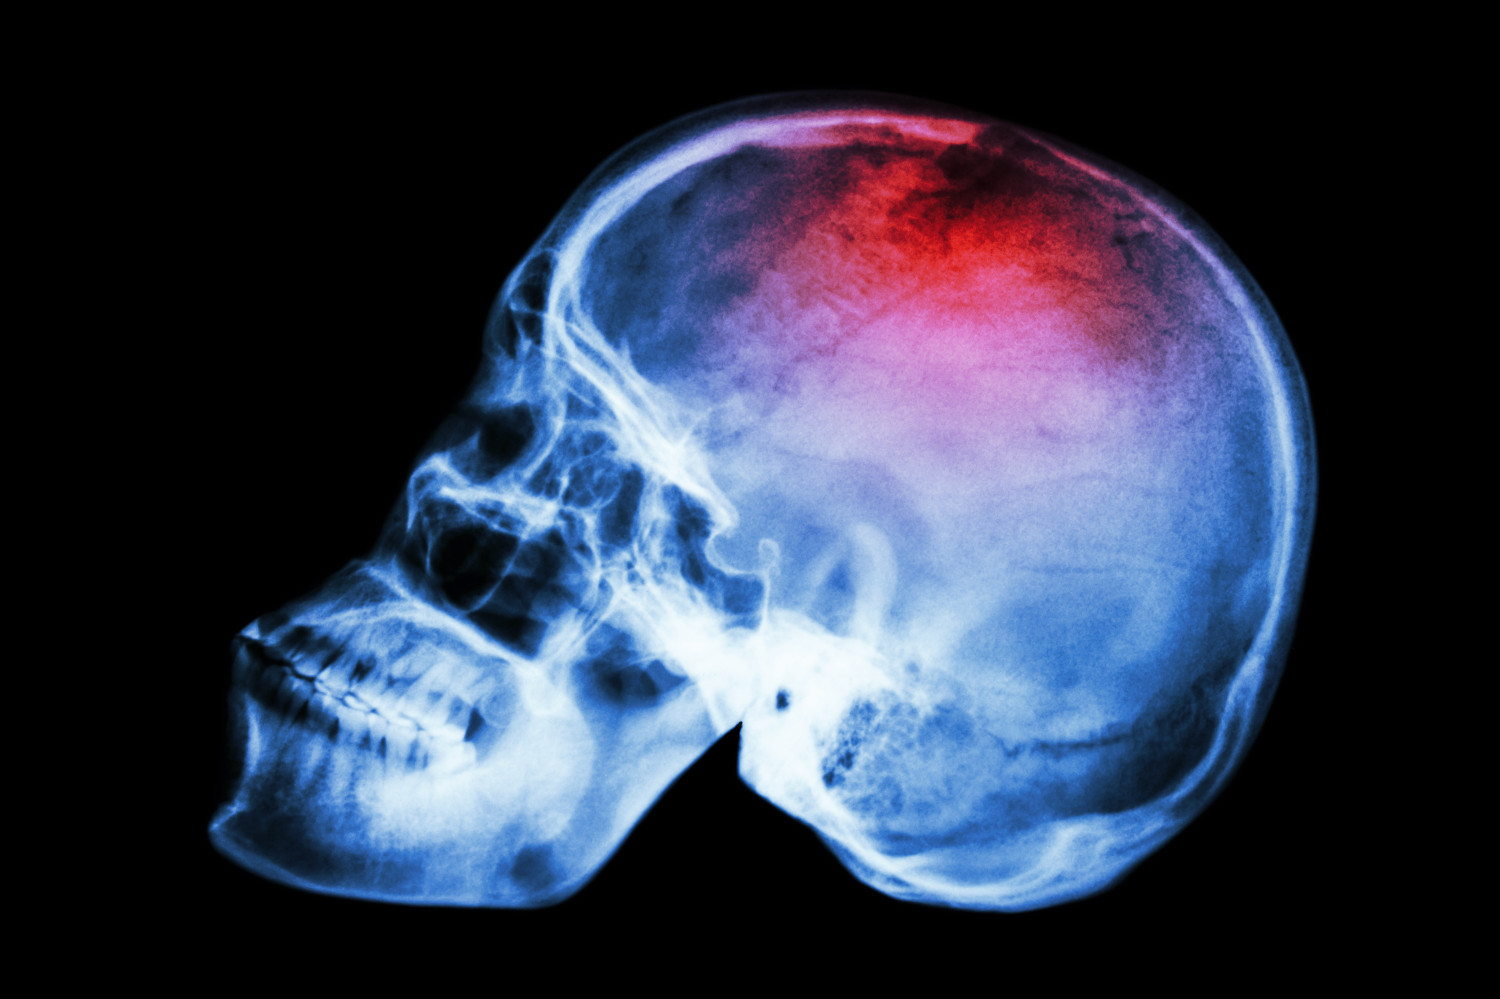

Названы наиболее эффективные классы препаратов при нелобарном внутримозговом кровоизлиянии

Ученые из Университета штата Огайо и Университета Цинциннати проанализировали эффективность различных классов антигипертензивных препаратов у пациентов с нелобарным внутримозговым кровоизлиянием. Результаты исследования опубликованы в журнале JAMA.